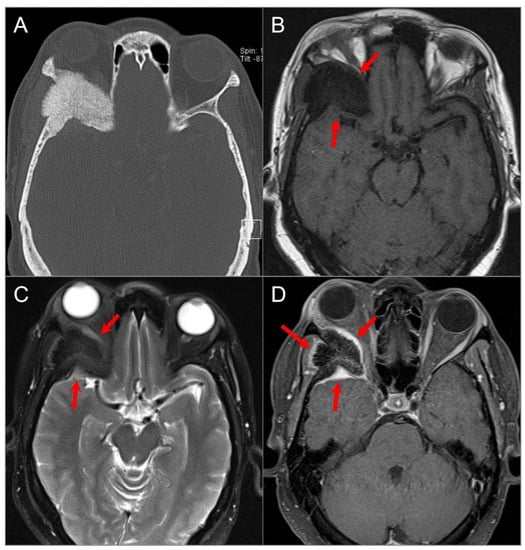

4.4. Posterior Skull Base Tumors

4.4.1. Chordoma

4.4.4. Endolymphatic Sac Tumor

4.4.5. Paraganglioma